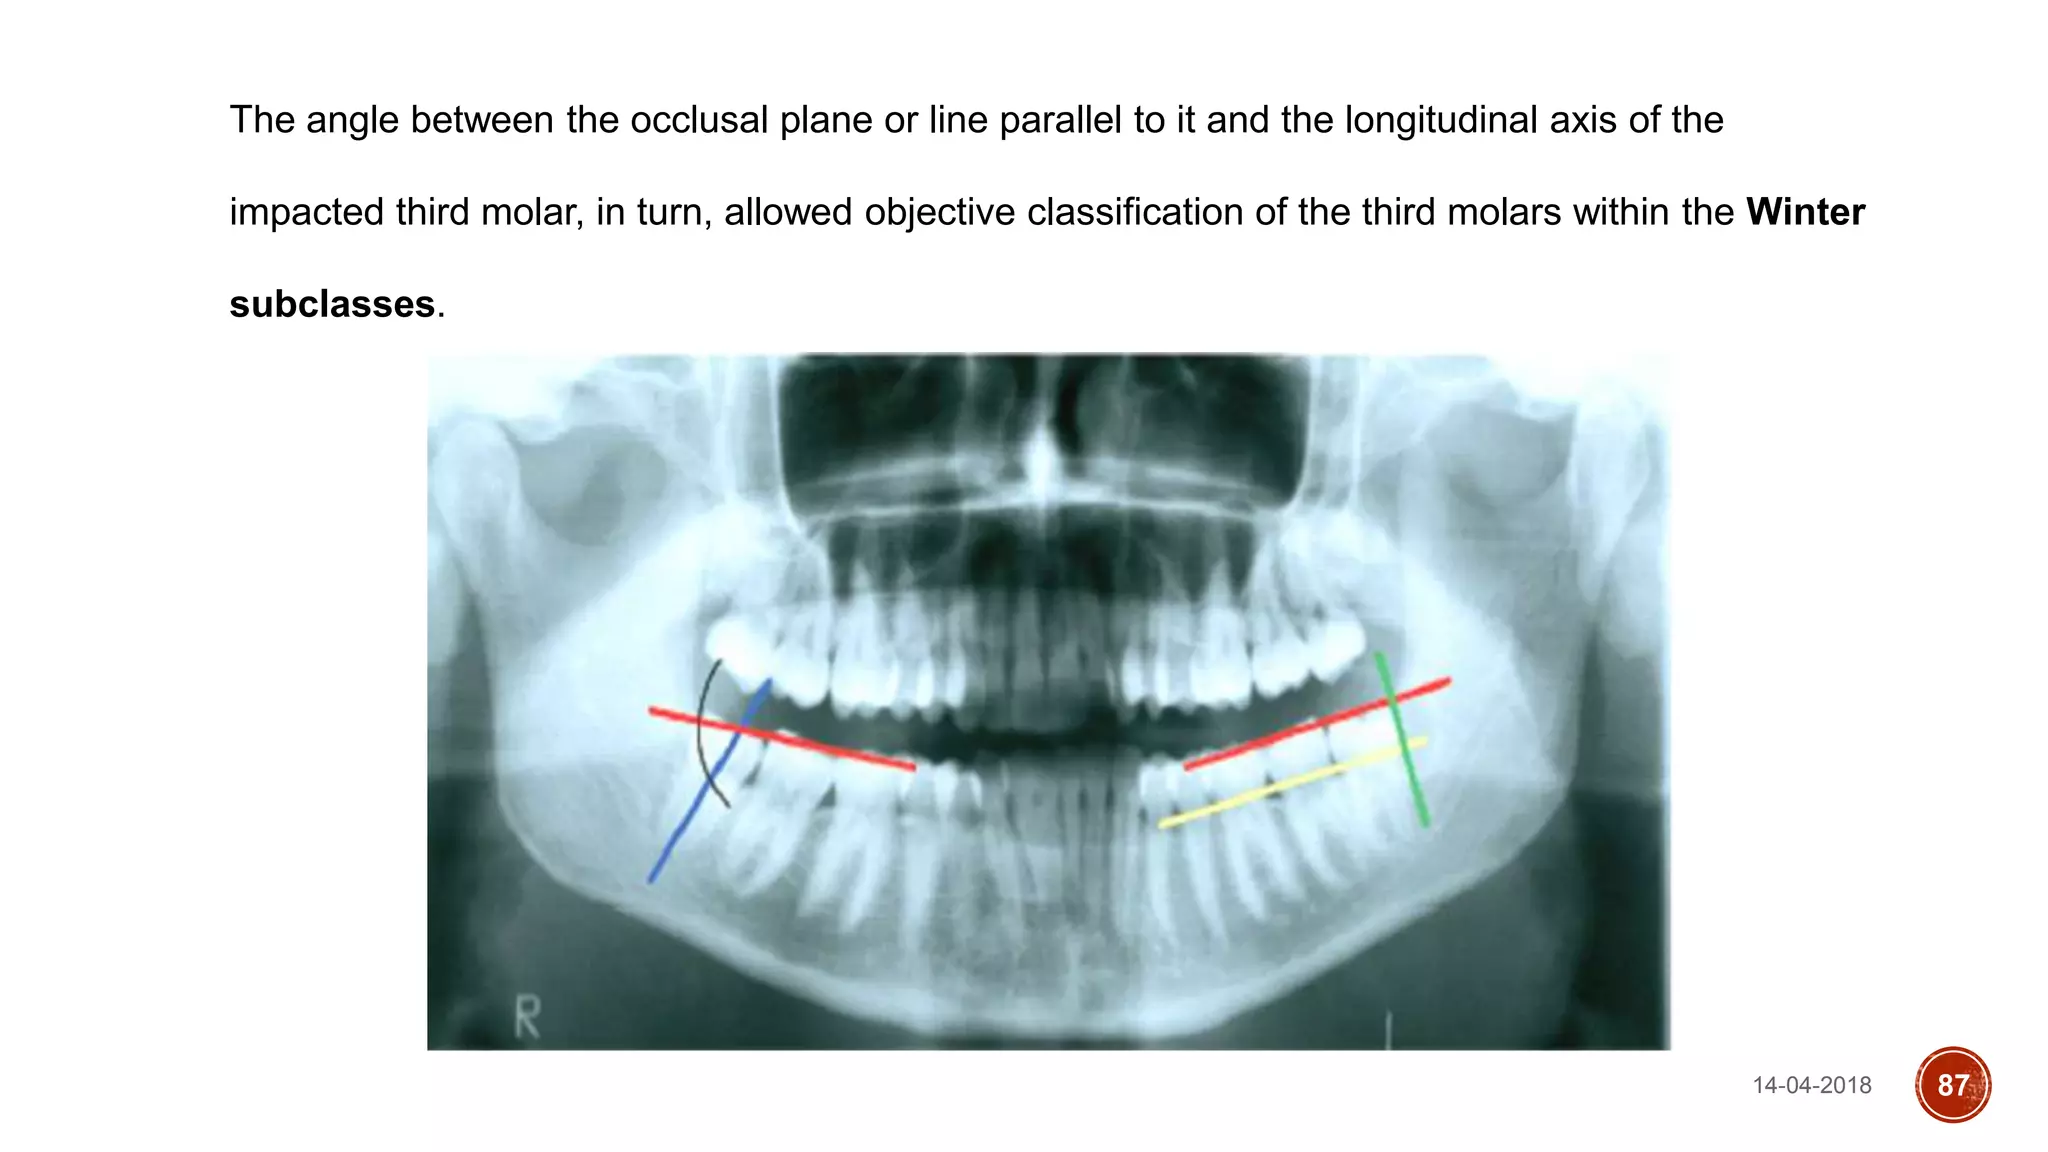

The angle between the occlusal plane or line parallel to it and the longitudinal axis of the

impacted third molar, in turn, allowed objective classification of the third molars within the Winter

subclasses.